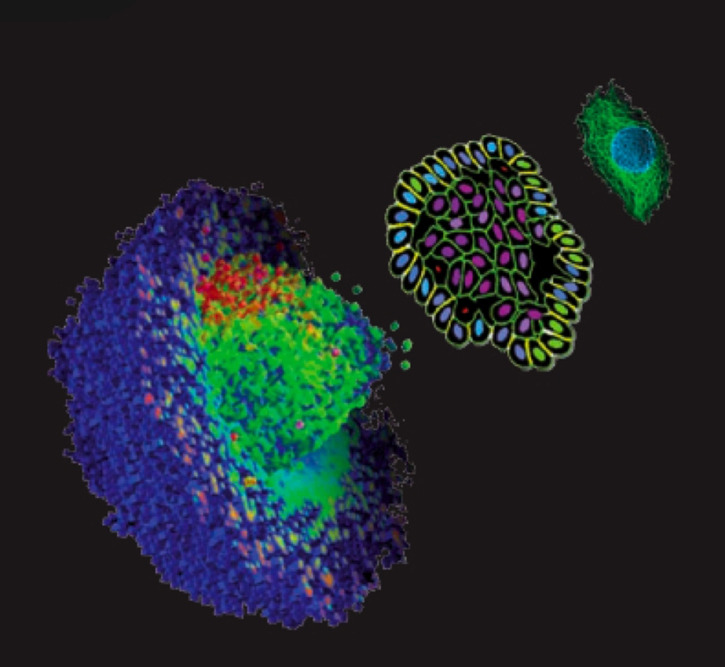

In a recent report, researchers at Johns Hopkins Kimmel Cancer Center have released their new studies on cancer - which they are doing with the help of evolutionary game theory! Their goal is to figure out how cells collaborate within a tumor and make energy, and with that, identify the best time to disturb the metastatic cancerous process.

Game theory is generally used to predict how humans interact with each other in situations of cooperation and conflict. But scientists are discovering that it can be used to model many other interactions as well, including to foretell cell-to-cell interactions in cancerous tumors.

Tumor cells have various cooperative and competitive states which vary as the tumor grows. Applying game theory to this process, the scientists found that there are a series of critical periods, based on mutation rates in which the cells in the tumor change their game-like strategy.

In this newfound window, scientists think that the tumor can be particularly vulnerable. With more research, game theory can calculate to help identify the ideal time to disrupt the growth of cancer cells and increase the efficiency of anticancer drugs.

Some tumor cells may stimulate surrounding normal cells to release lactate which, in turn, feeds the tumor. A therapy that disrupts this system, while it is in a critical transition, could help to shut down the tumor and pave the way for anti-cancer therapies to take effect.

Though scientists are just starting out with applying the mathematics of game theory to cancerous cells and more research needs to be done to find out if this occurs in all tumors, this scientific advancement is already taking another step in the right direction - opening the door to finding out more about the progressive nature of cancer.

- Image: Courtesy of Moffitt Cancer Center. Individual Cell-Based Model for Tumor Growth.